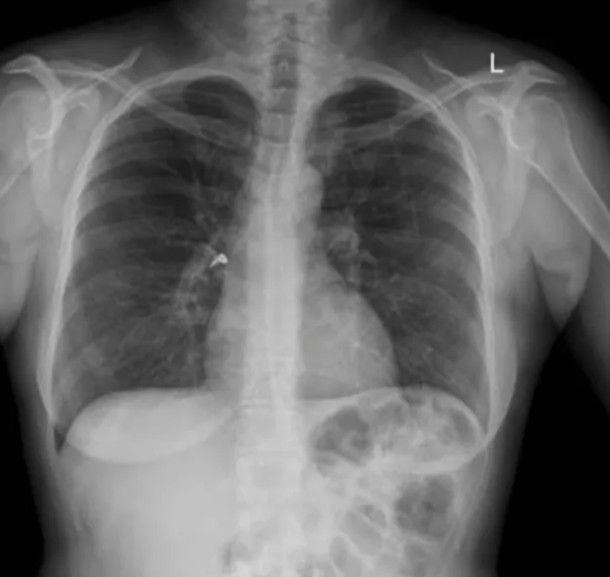

A woman in Australia accidentally inhaled an earring at a New Year's Eve party. The 41-year-old woman, who had asthma, reached into her purse for her inhaler when she began to wheeze during the New Year's festivities. Unbeknownst to her, a loose earring from her purse had become lodged in the inhaler, and she inhaled it when she used the device. The earring scratched the back of the woman's throat, causing her to wheeze more and cough up blood, before it became lodged in her right bronchus. Thankfully, the doctors were able to remove the earring, and the woman healed quickly. By: https://www.livescience.com/37919-oddest-medical-case-reports.html